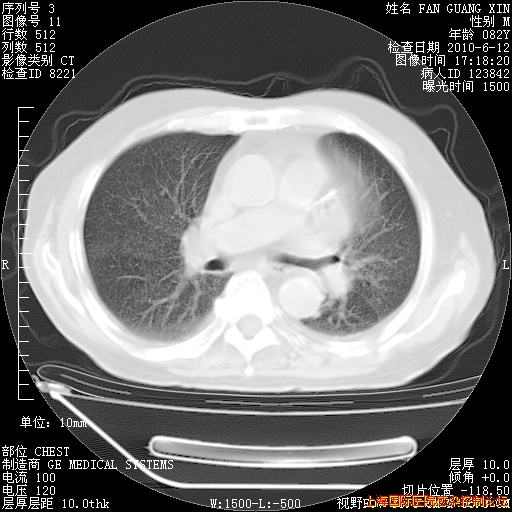

补发6月12日肺部CT肺窗

6月12日肺窗

整整相隔30天的肺部CT好像有所好转啊。甲强龙减量第3天,需要观察体温。

海管,自昨日你和我通完话后,不知您岳父消化道症状有无缓解?体温怎样?阅读7.12日胸部ct,个人认为目前激素治疗是有效的,甲强龙减量是适宜的。因在抗痨治疗,需密切观察肝功、肾功能和血常规。不过,老年、长期住院和大量使用激素,很担心菌群失调发生